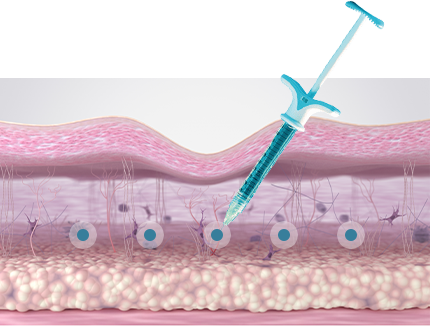

70% of Collagen Structure

Glycine, proline, and lysine account for approximately 70%

of the collagen structure. During fibroblast metabolic activity,

these amino acids stimulate fibroblasts to promote collagen

production and support collagen synthesis, helping improve

skin firmness and structural integrity.